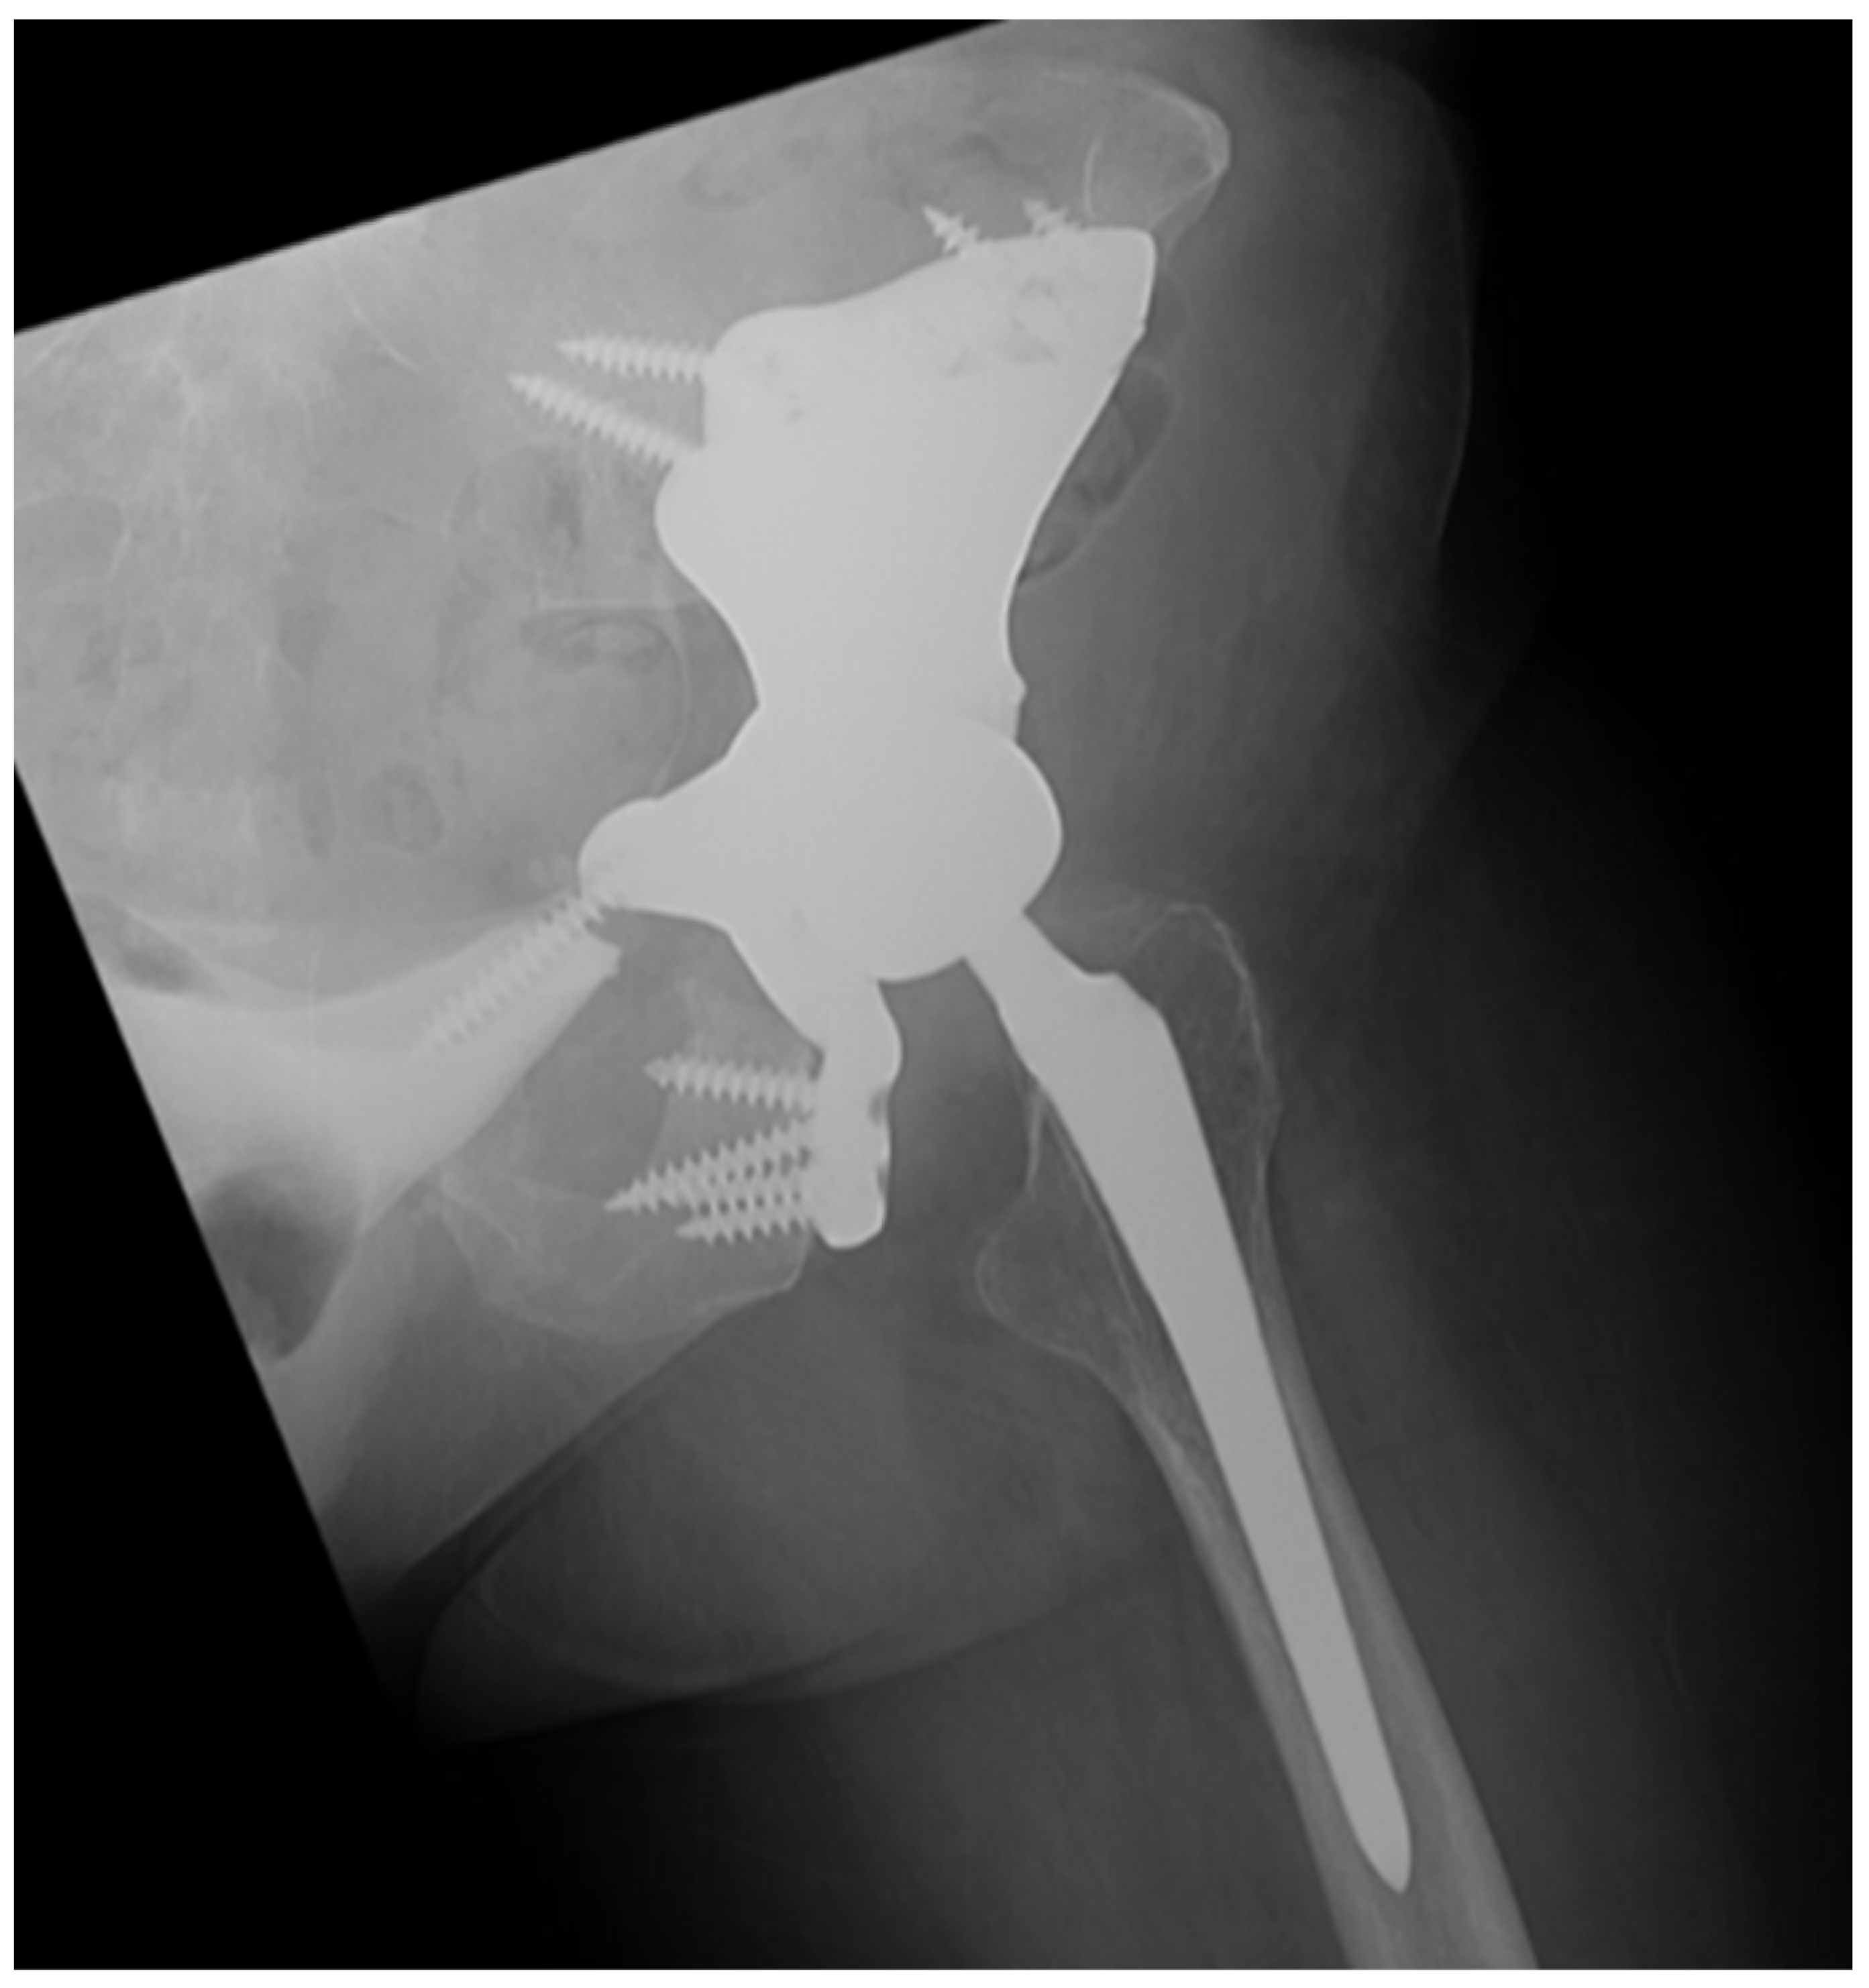

| Procedures Performed | Stage 1: L5-S1 anterior discectomy, anterior sacral osteotomy, fibula flap harvest Stage 2: sacrectomy, L3-pelvis PSIF, L5-pelvis ASF with vascularized fibula flap, VRAM flap | Stage 1: Rt T12-pelvis PSIF, L3-5 laminectomy, fibula flap harvest; Stage 2: L4, L5 vertebrectomy, sacrectomy, Lt type I internal hemipelvectomy, Lt L3-pelvis PSIF Stage 3: L3-pelvis ASF with vascularized fibula flap | Lt type I-II internal hemipelvectomy, custom endoprosthetic pelvic and hip joint reconstruction | Lt Type I internal hemipelvectomy, vascularized fibula autograft reconstruction | Stage 1: L3-S3 laminectomy, L5 vertebrectomy, L3-pelvis PSIF; Stage 2: Lt type I internal hemipelvectomy, Lt partial sacrectomy, L5-pelvis ASF with vascularized fibula autograft | L5-S1 laminectomy, partial sacrectomy, Lt ilium osteotomy, pedicled Rt gluteus maximus flap |